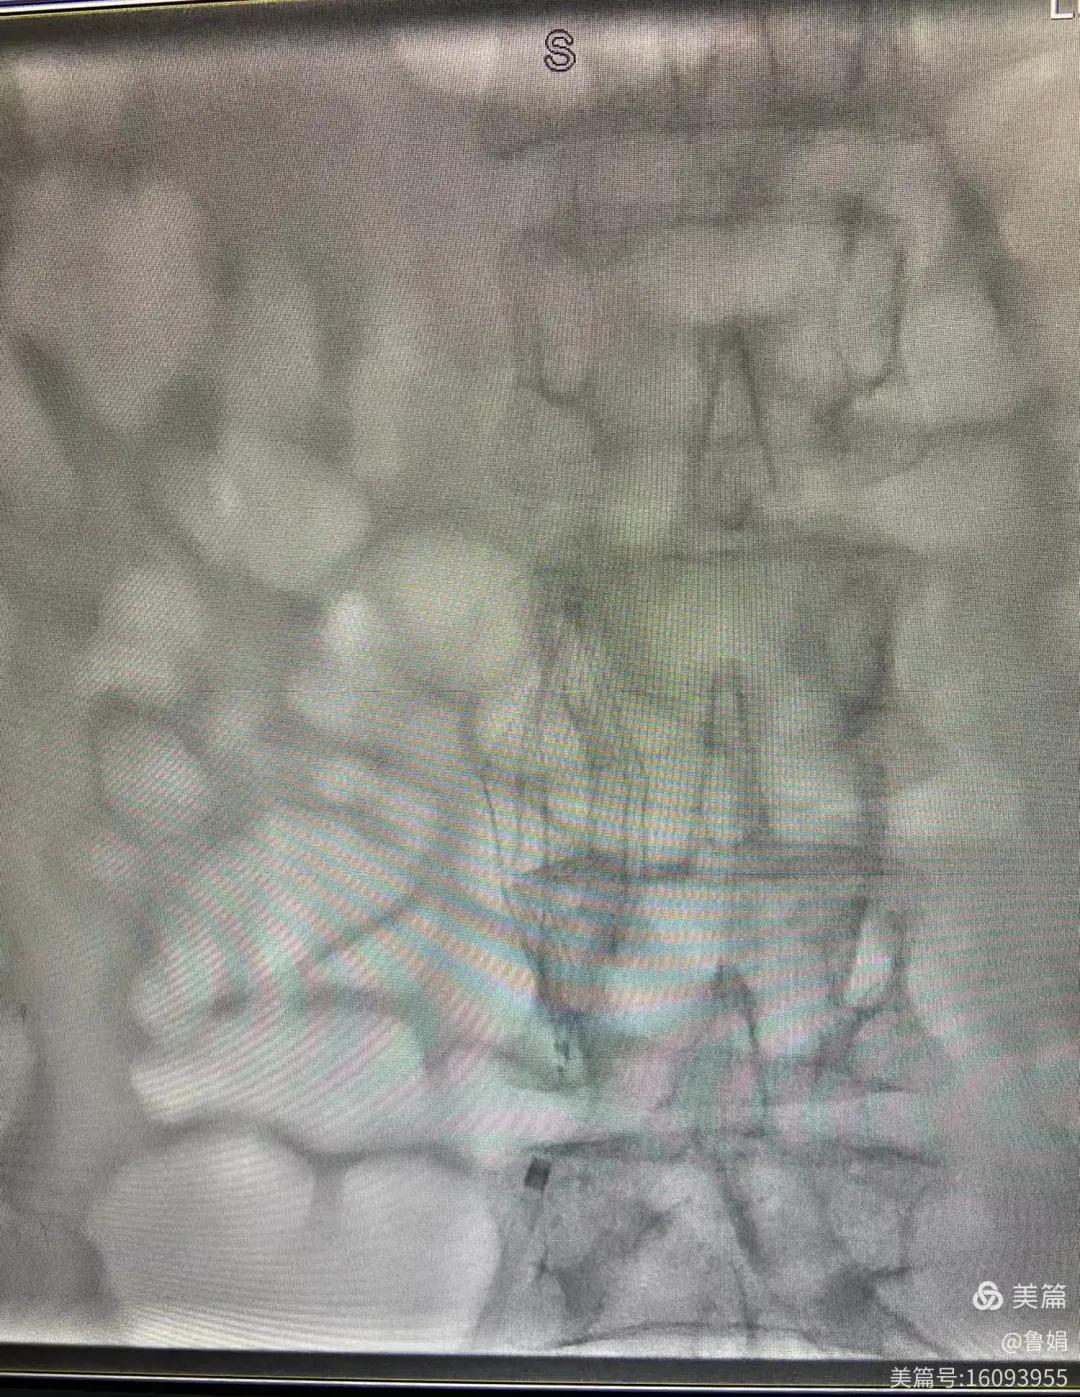

圖片術(shù)后濾器順利植入

經(jīng)認(rèn)真查看患者病例,探討患者病情及術(shù)中潛在風(fēng)險(xiǎn)因素,多科會(huì)診后急診為患者開(kāi)展介入手術(shù),術(shù)中周創(chuàng)業(yè)副主任、孫亞中副主任中醫(yī)師二人通力合作,手術(shù)順利,病人術(shù)中出血少,生命體征平穩(wěn),現(xiàn)在腦二科病房繼續(xù)對(duì)癥治療。(介入中心:魯娟)